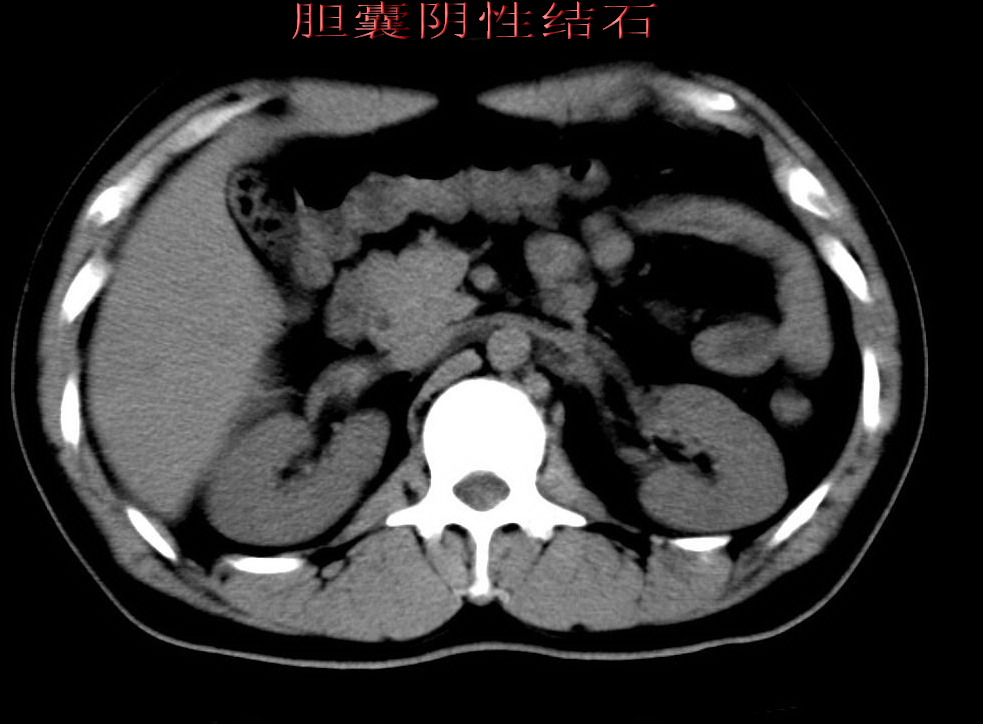

标题: 胆囊阴性结石ct图片

好啊!我有ct的插进来啊,楼主请允许噶。

石榴籽样阴性结石,学习了!

胆囊石榴籽样结石。